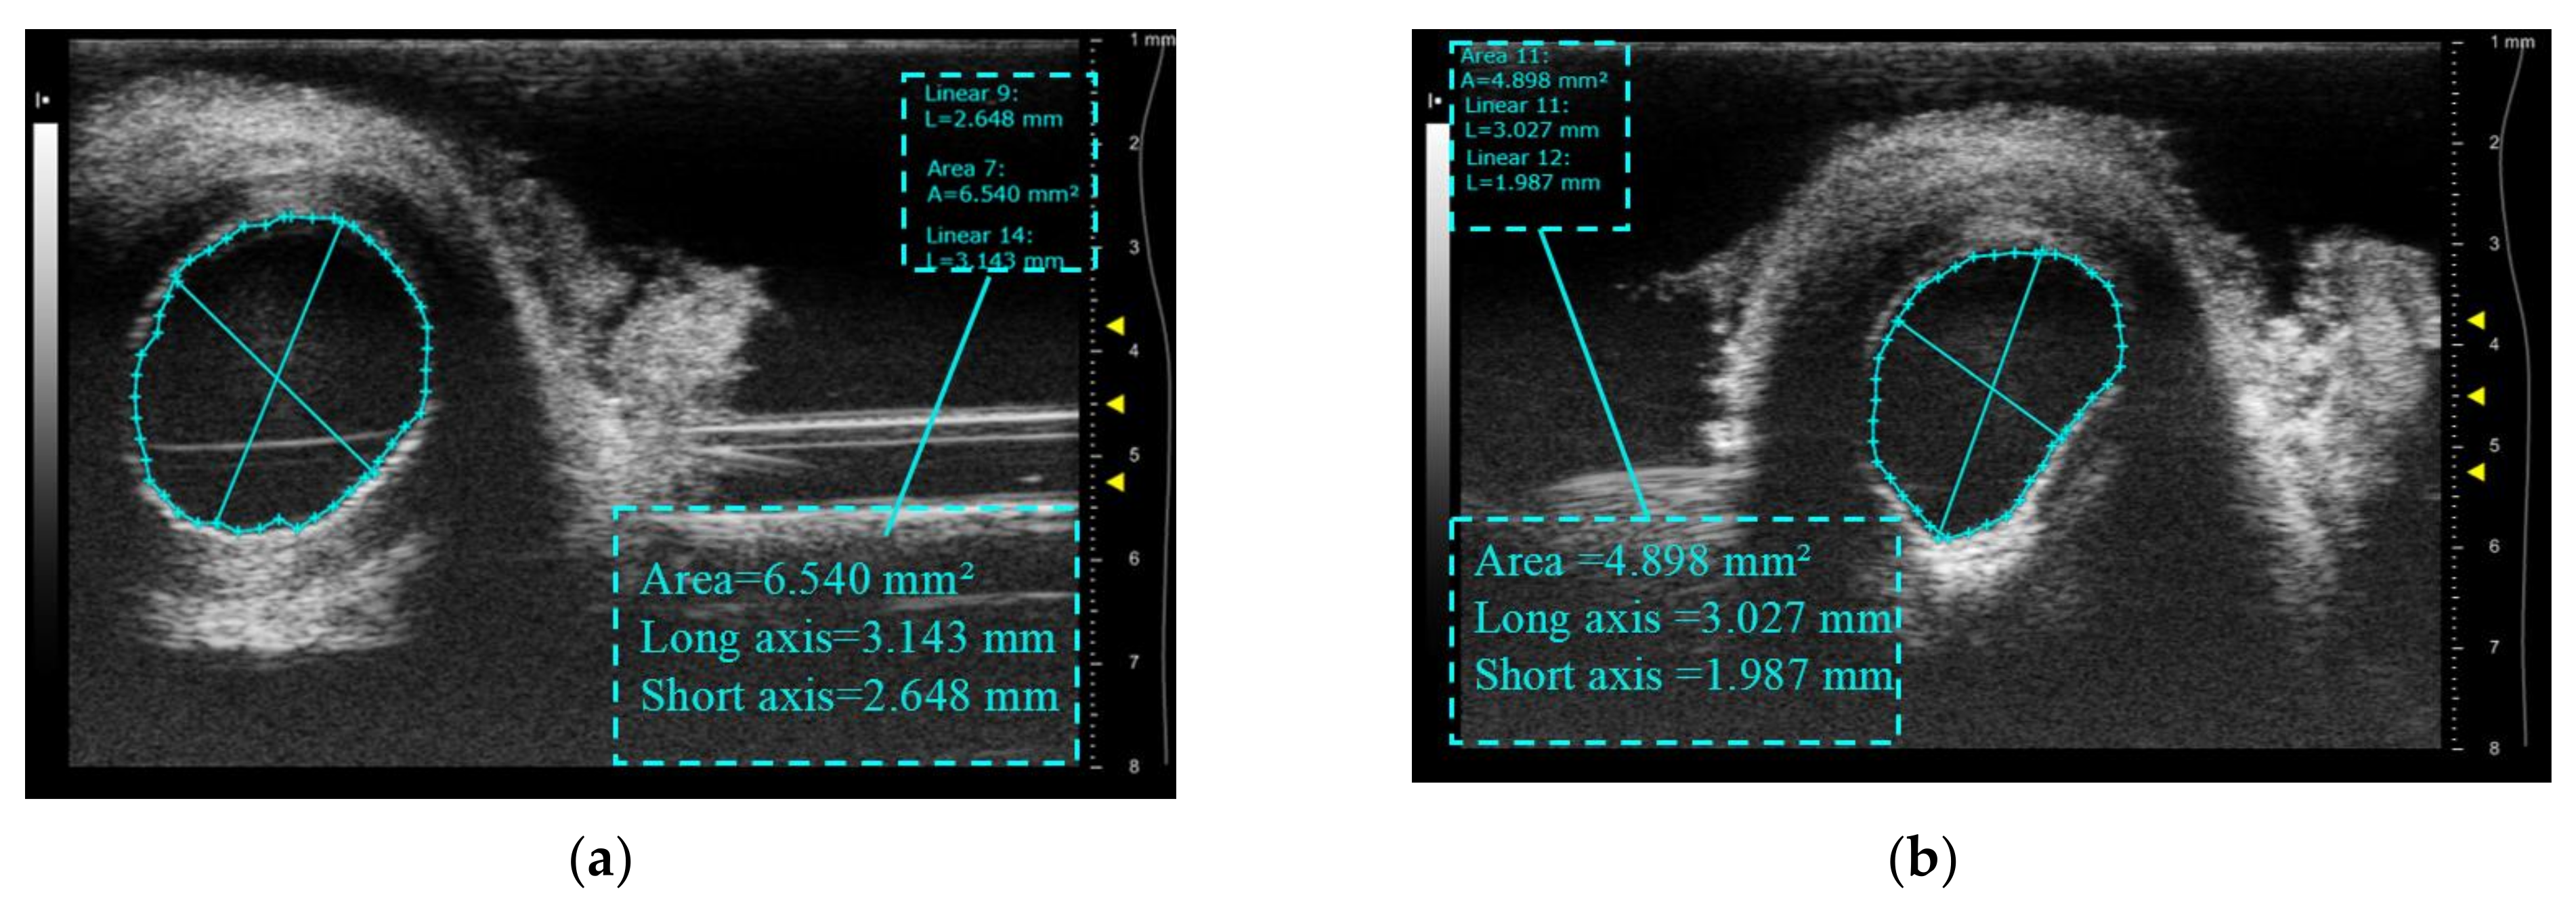

Figure 15 displays a comparison of vascular imaging before and after treatment of the inferior tube wall using a commercial Vevo 2100 small animal ultrasound system in combination with a 50 MHz center frequency linear array imaging probe. The untreated porcine artery area in Figure 15a is approximately 6.54 mm2, with a maximum diameter of 3.143 mm and a minimum diameter of 2.648 mm. The treated pig artery section is displayed in Figure 15b, with an area of approximately 4.898 mm2, a maximum diameter of 3.027 mm, and a minimum diameter of 1.987 mm. The cross-sectional area decreases by 25% after the treatment, while the minimum diameter decreases by 24%. The inferior wall of the vessel indicates notable shrinkage, consistent with the result of the high-light denaturation on the inferior surface of the vessel after treatment in Figure 14c, thereby confirming the effectiveness of this innovative high-frequency ultrasound-guided integrated system for varicose vein ultrasound therapy under similar working conditions.

Figure 15.

Cross-sectional ultrasound comparison images of blood vessels before and after treatment: (a) before treatment; (b) after treatment.